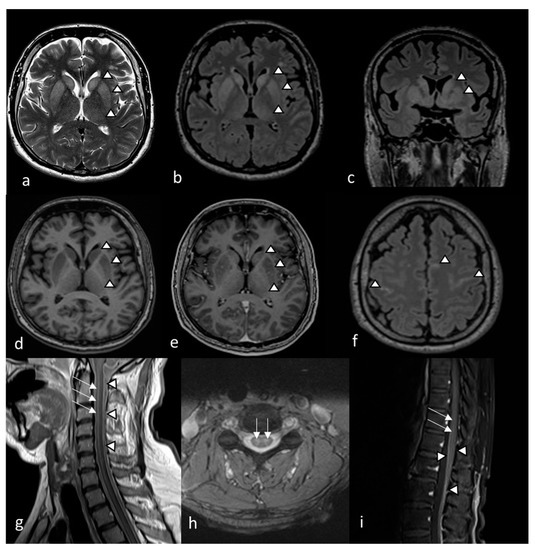

2. Case Description